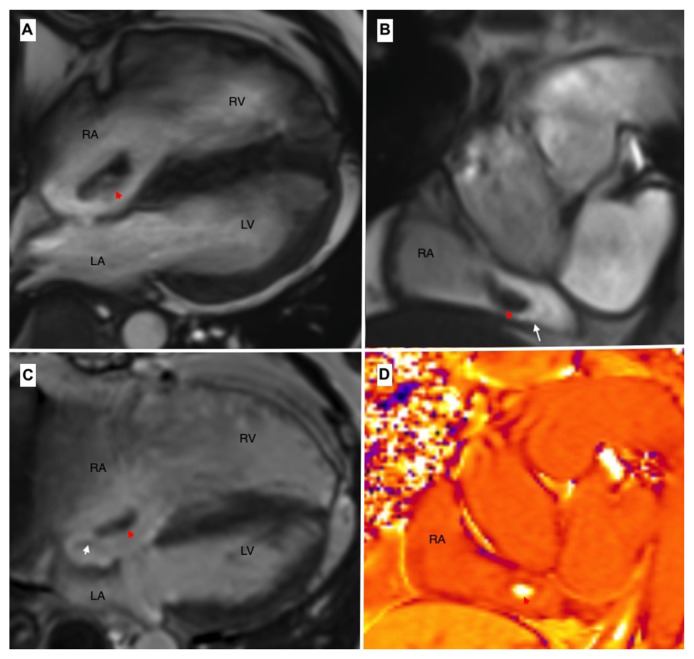

Atrial septal defects are among the most prevalent congenital anomalies necessitating surgical intervention. Thrombus formation is a recognized complication that is typically characterized by an embolic event following patch-based repair. However, thromboembolic complications following primary repair of atrial septal defects are exceedingly uncommon. Minimally invasive surgery is a suitable alternative to redo sternotomy. We present a 46-year-old man who was diagnosed with a right atrial mass eight years following the patch repair of an atrial septal defect and underwent a successful minimally invasive redo surgery.

Abstract Image